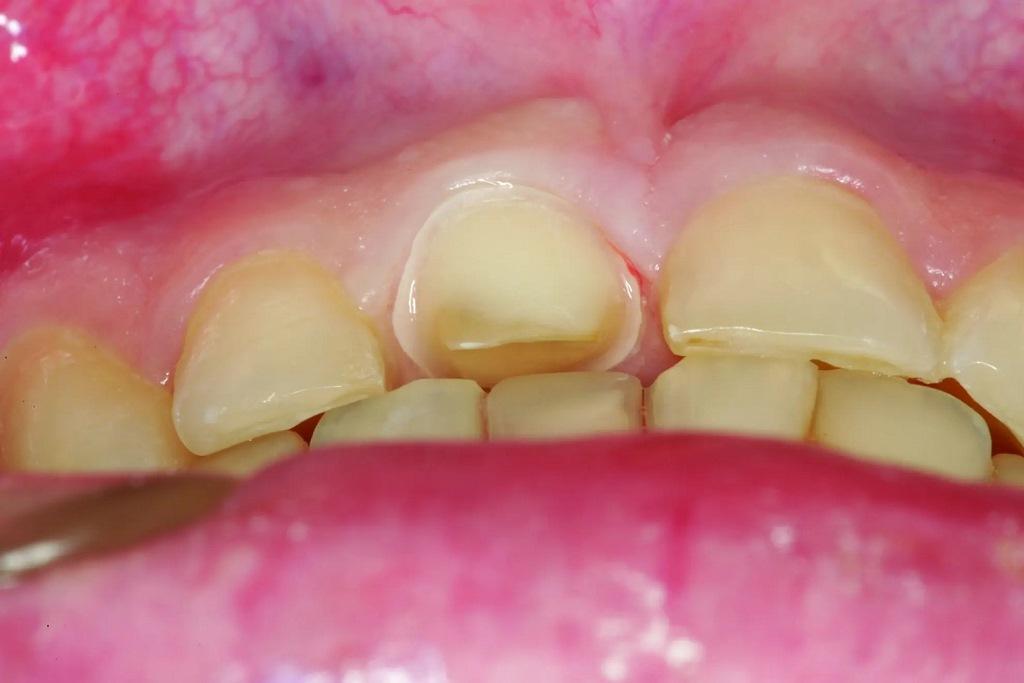

А как насчет выравнивания зубов-антагонистов? На режущих краях зубов 31 и 41 (фото 2) наблюдался чрезмерный износ. Со стороны резцов был виден значительный износ всех краев нижней челюсти из-за окклюзионного заболевания, которое часто наблюдается, но не лечится (фото 3). Также зуб 41 располагался на лицевой стороне таким образом, что при выступающей экскурсии он преждевременно соприкасался с небной поверхностью зуба 11, создавая дополнительную нагрузку как на небную поверхность, так и на резцовый край зуба 11, прежде чем соединиться с остальной частью переднего сегмента верхней челюсти. Это демонстрирует, что решение этих проблем реставрационными методами включает в себя нечто большее, чем просто исправление сколов композитной реставрации.

Фото 2: Зубы выступают вперед, что свидетельствует о чрезмерном износе зуба (41), расположенного напротив зуба 11, что указывает на гиперфункцию и повышенную функциональную нагрузку на восстановленную область.